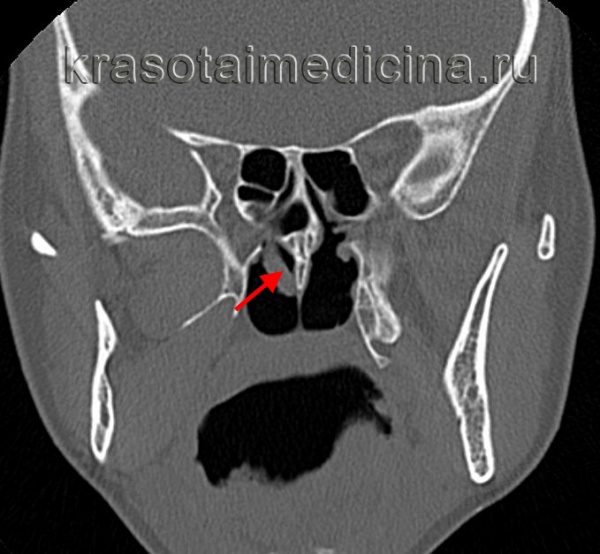

(Слева) При корональной «костной» КТ у девочки 14 лет с муковисцидозом (МВ) определяются типичные признаки ПНП, в т.ч. снижение пневматизации ячеек решетчатой кости справа за счет полиповидного материала, распространяющегося также в полость носа, и доброкачественное ремоделирование костей. Обратите внимание на большое мукоцеле решетчатой кости слева с распространением в орбиту и гипоплазию правой лобной пазухи.